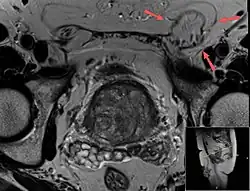

Medical imaging

A physician may diagnose an inguinal hernia, as well as the type, from medical history and physical examination.[20] For confirmation or in uncertain cases, medical ultrasonography is the first choice of imaging, because it can both detect the hernia and evaluate its changes with for example pressure, standing and Valsalva maneuver.[21]

When assessed by ultrasound or cross sectional imaging with CT or MRI, the major differential in diagnosing indirect inguinal hernias is differentiation from spermatic cord lipomas, as both can contain only fat and extend along the inguinal canal into the scrotum.[22]

On axial CT, lipomas originate inferior or lateral to the cord, and are located inside the cremaster muscle, while inguinal hernias lie anteromedial to the cord and are not intramuscular. Large lipomas may appear nearly indistinguishable as the fat engulfs anatomic boundaries, but they do not change position with coughing or straining.[22]